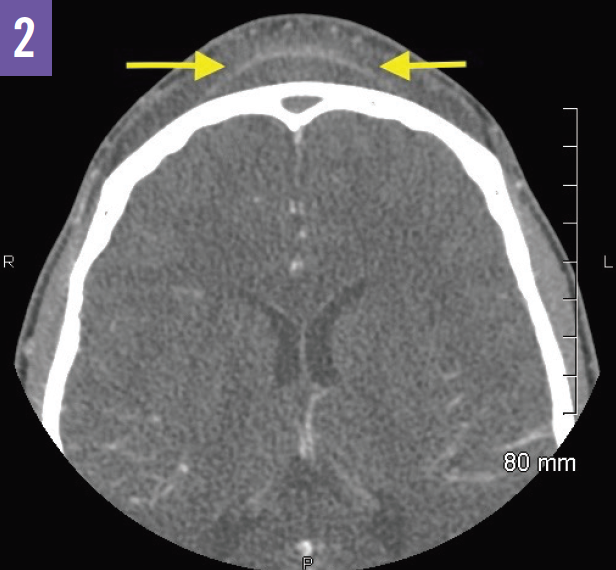

A contrast-enhanced CT of the sinuses performed after admission revealed complete opacification of the frontal sinuses and thinning of the inner table of the right frontal sinus. There was expansion of the bony margins of the right frontal sinus and a well-marginated collection in the right frontal sinus with a thin hyperdense rim (Figure 1). A thin-walled subgaleal collection was noted in the forehead at the midline overlying the outer table of the frontal sinuses (Figure 2). These CT findings were consistent with severe acute sinusitis with spread of infection into the soft tissues of the forehead and nasal bridge, or Pott puffy tumor. While there was no evidence of subdural empyema, a contrast-enhanced magnetic resonance imaging (MRI) scan of the brain was recommended to evaluate for subtle changes such as dural enhancement.